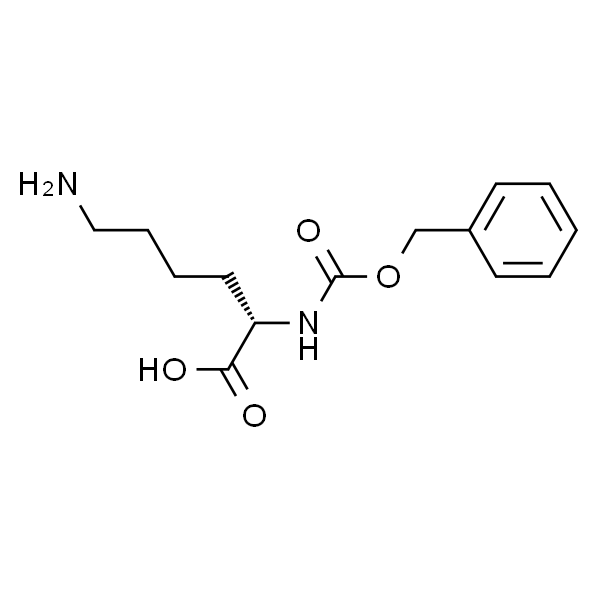

中文名称:

沙芬酰胺

英文名称:

Safinamide

CAS No.:

133865-89-1

分子式:

C₁₇H₁₉FN₂O₂

分子量:

302.34

沙芬酰胺用途Safinamide (EMD 1195686; FCE 26743)是可逆的MAO-B抑制剂,IC50为98 nM,比对MAO-A的抑制性高5918倍。